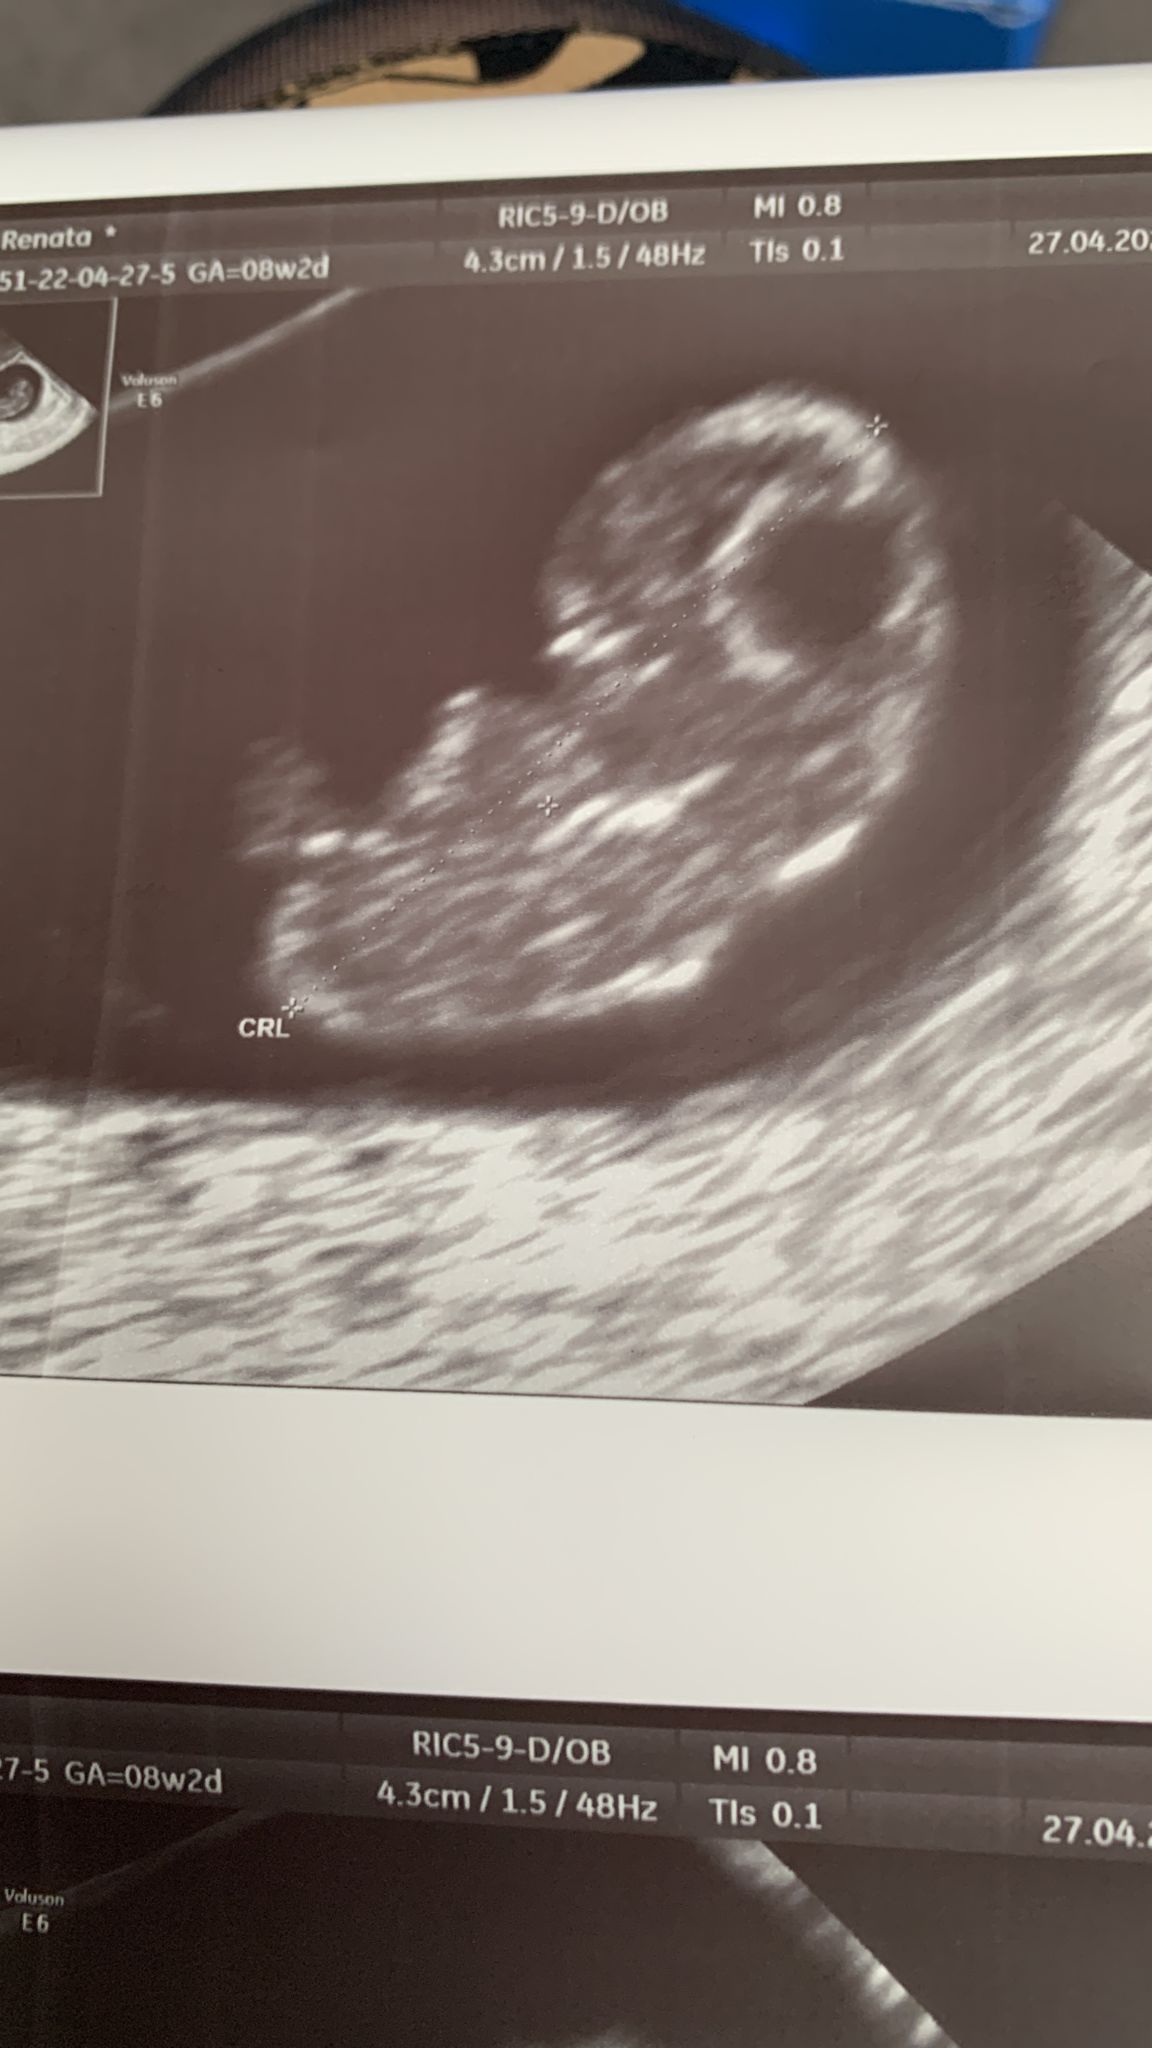

Dziewczyny, moja wizyta tez super, wszystko jest w porządku, dzidziuś ma 1,79 cm słyszałam bijące serduszko, jestem mega szczęśliwa 😍

1952D8D8-622A-4410-9F3E-9B6B7F7E8935.jpeg